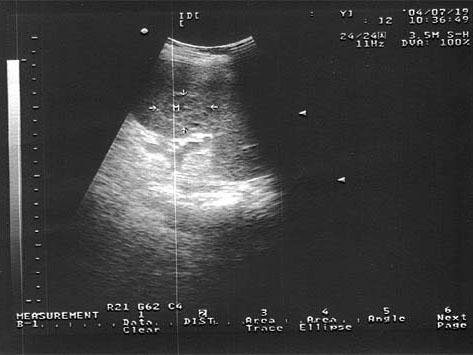

问题 女,19岁,有淋巴瘤病史。结合超声声像图,诊断为?(?)

选项 A.脾淋巴瘤 B.脾血管瘤 C.脾结核 D.脾错构瘤 E.脾脓肿

答案 A